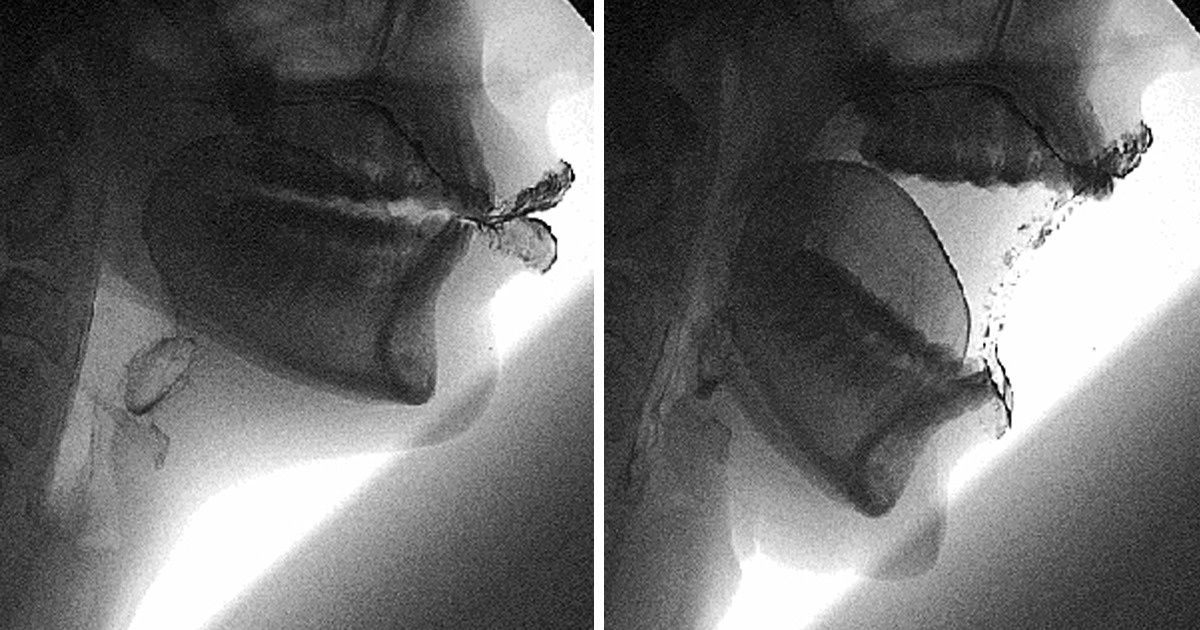

Comme le disent les scientifiques, dans le ventre de la mère, un futur individu passe par toutes les étapes du développement évolutif. Donc, nous avons tour à tour une queue, des branchies et des membranes entre les doigts. Peut-être le savais-tu déjà mais sans l’avoir vu en image.